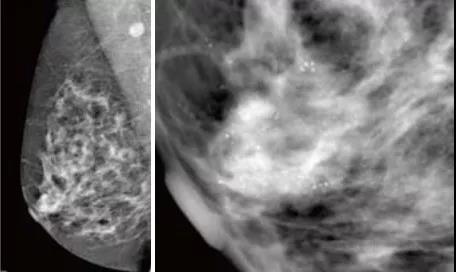

整合了GE創(chuàng)新的乳腺斷層攝影技術(shù)、乳腺對(duì)比增強(qiáng)技術(shù)、立體定位活檢技術(shù),合三為一,貫穿乳腺篩查、診斷、治療全路徑,為乳腺癌早期發(fā)現(xiàn)、早期診斷以及治療和術(shù)后監(jiān)控全流程帶來了完整解決方案。Senographe Essential全數(shù)字化平板乳腺機(jī)。與以往乳腺鉬靶機(jī)及其它乳腺檢查方法比較,該機(jī)對(duì)乳腺疾病診斷是劃時(shí)代的進(jìn)步,是識(shí)別早期乳腺癌的“火眼金睛”。

GE 平板數(shù)字乳腺機(jī)拍攝的右乳MLO,清晰顯示早期乳腺癌的沙粒樣鈣化,

此時(shí)乳腺觸診并沒有任何異常